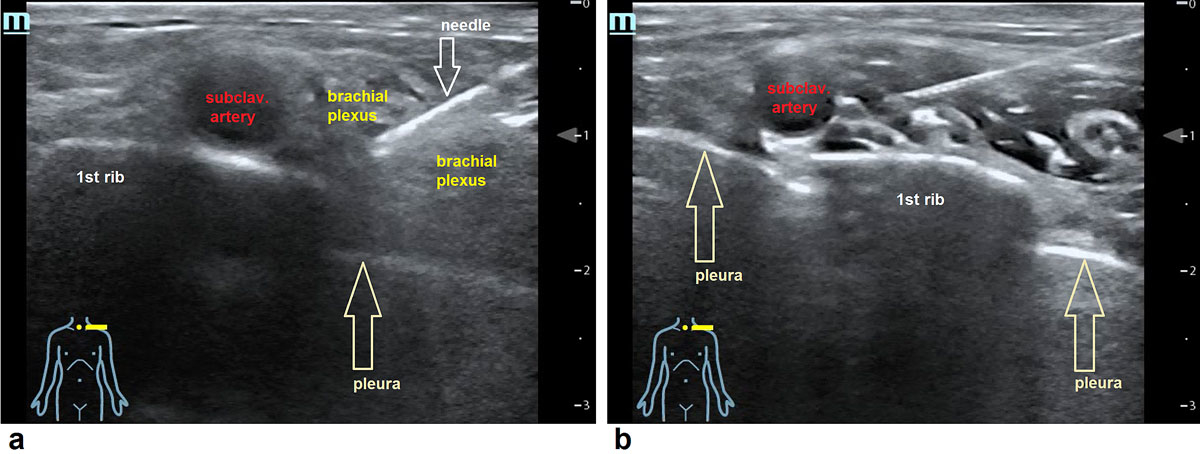

Patients in the intervention group received UGRA in the form of a supraclavicular or an axillar block (figs 1–3 ). A HITACH Hi Vision AVIUS with a 50-mm linear-array probe (5.0–13.0 MHz) or a MINDRAY TE7 with 16 MHz linear transducer was used. The regional anaesthesia was 13 to 40 ml bupivacaine 0.5% or prilocaine 2% and was applied with a PAJUNK SonoPlex Stim cannula 22G x 50 mm. It was single-dose regional anaesthesia without additional stimulation. To perform the UGRA, emergency physicians had to attend a 2-day course in ultrasound-guided regional anaesthesia. The same ultrasound set-up was used to guide the reposition. A long-axis view generated the necessary information for this procedure (fig. 4).

Figure 3 Ultrasound image of the brachial plexus. (a) Needle is placed between the nerves of the brachial plexus in the supraclavicular region above the first rib. (b) After injection of 15 ml local anaesthetic the nerves are surrounded with the fluid.